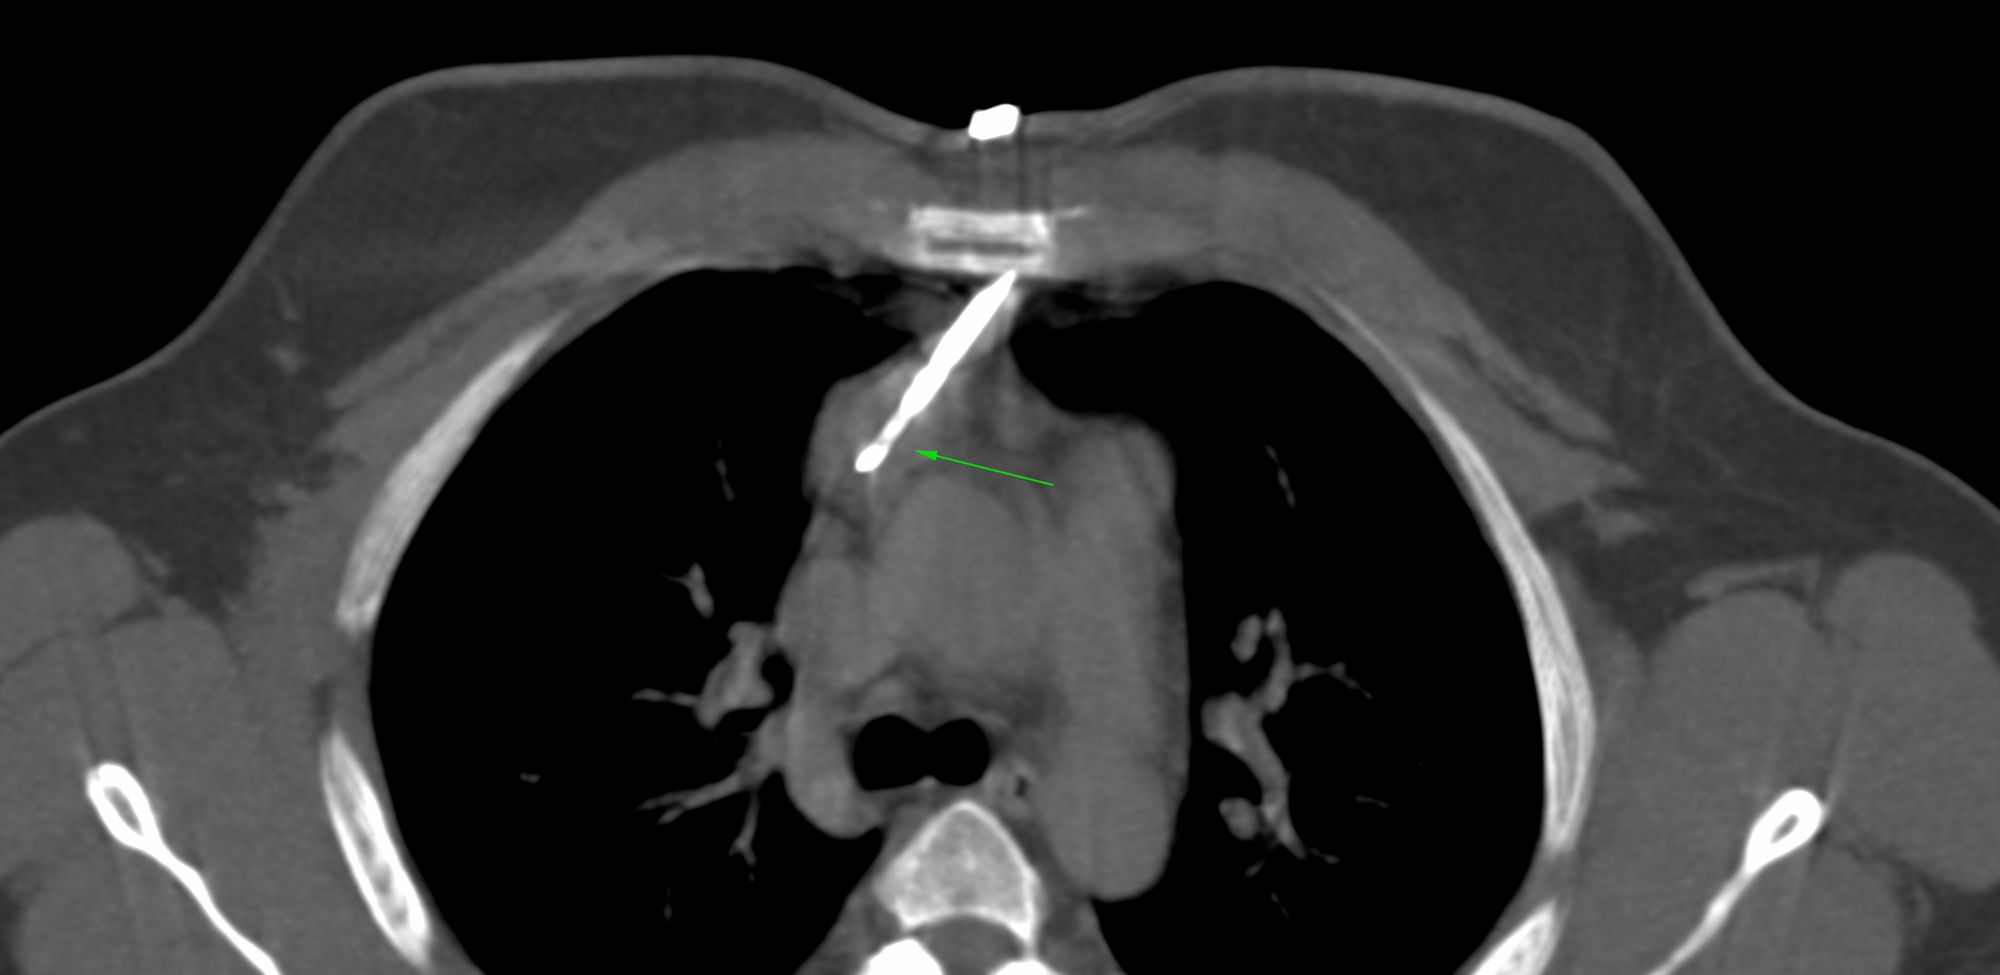

Case 31: Subcarinal Node Biopsy - Transpulmonary Approach

Bhavin Jankharia - 10 May 2021